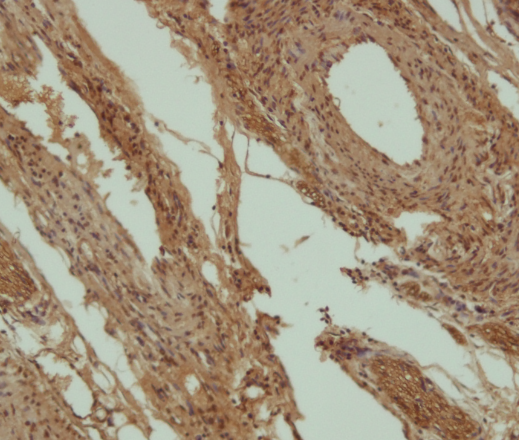

请做过免疫组化的进来鉴定一下我的ICH图片~ 已有5人参与

免疫组化 |